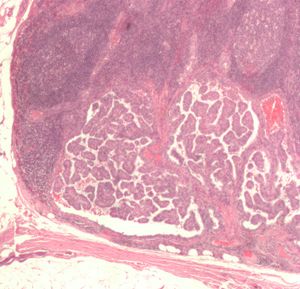

| صورة مجهرية (عرض عالي الطاقة) من حليمي سرطان الغدة الدرقية مما يدل على ملامح التشخيص (المقاصة النووية ونوى المتداخلة). صبغة الهيماتوكسيلين والأيوزين. | |